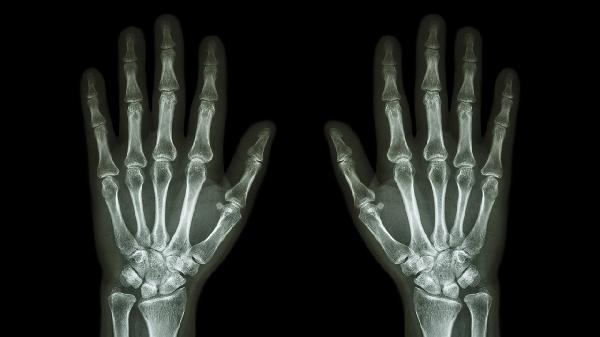

病理性骨折可能由骨質(zhì)疏松、骨腫瘤、骨感染、骨代謝異常、長期使用糖皮質(zhì)激素等原因引起,病理性骨折可通過藥物治療、手術(shù)治療、物理治療、營養(yǎng)支持、原發(fā)病控制等方式治療。